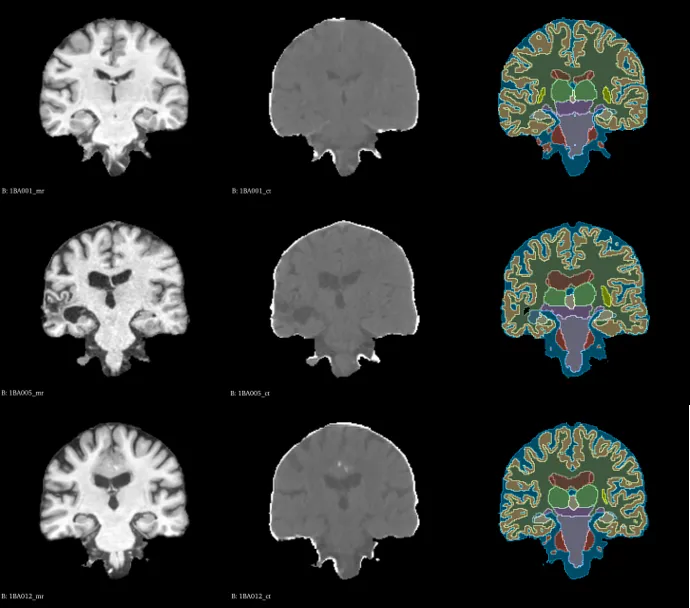

SR for Medical Imaging